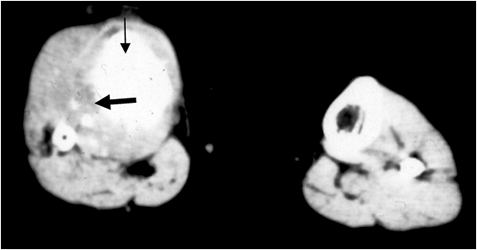

Fig 70 B. Osteosarcoma.

TAC axial. Engrosamiento de la tibia proximal, con formación de matriz osteoide. (Flecha delgada). Existe masa de tejidos blandos y destrucción de la cortical (Flecha gruesa), por osteosarcoma.